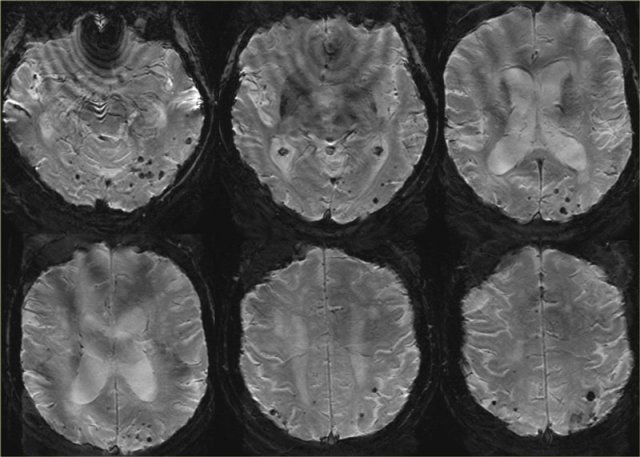

Cerebral Amyloid Angiopathy Cerebral Amyloid Angiopathy

Cerebral Amyloid Angiopathy (CAA)

Dementia may be the clinical presentation in CAA, a condition in which ?-amyloid is deposited in the vessel walls of the brain.

The result is hemorrhage, usually microhemorrhages, but also subarachnoid hemorrhage or lobar hematomas may occur.

On MR, the T2* sequence will show multiple microhemorrhages, typically in a peripheral location (as opposed to hypertensive microhemorrhages, which are usually more centrally located, e.g. in the basal ganglia and thalami).

In addition, FLAIR will reveal moderate to sever white matter hyperintensities (Fazekas grade 2 or 3)

T2* images in a patient with CAA show multiple peripherally located microbleeds.

T2* images in a patient with CAA microbleeds.

Cerebral Amyloid Angiopathy

T2* images demonstrate multiple lobar microbleeds in a patient with CAA.